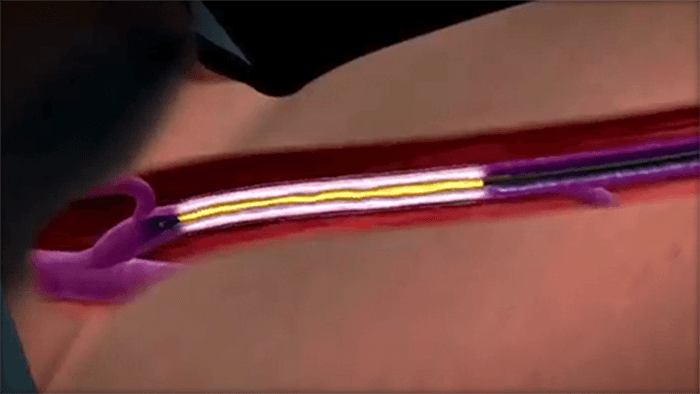

Ablation Therapy

A minimally invasive treatment that uses lasers, radiofrequency, non-thermal ablation or mechanochemical ablation to shut down large varicose veins in the legs.